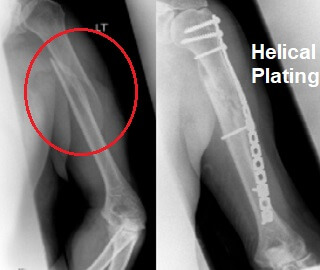

View Humerus Bone Fracture Plate UK. Most fractures of the proximal humerus can be treated without surgery if the bone fragments are not shifted out of position (displaced). A humerus fracture is a break somewhere along the upper arm bone.

It is the longest bone of the upper extremity. The broken parts of the tibia line up and in severe cases, surgery may be necessary to make sure the bone heals properly. Humeral fractures can be classified into three types, depending on which.

Alibaba.com offers 996 humerus fracture plates products. The broken parts of the tibia line up and in severe cases, surgery may be necessary to make sure the bone heals properly. A humerus fracture is a break in the large bone of your upper arm. The humerus is the long bone in your upper arm that connects your shoulder joint to your elbow joint.